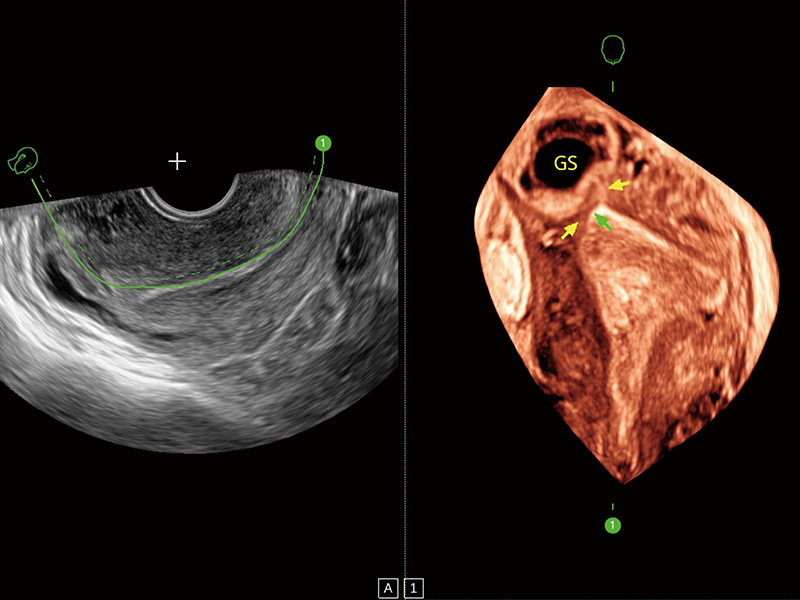

腔内容积探头

腔内三维成像技术获得显著提升,超大扇角在满足日常基础扫查的同时,支持卵泡自动测量及多种三维渲染模式,为您提供更多的诊断信息,尤其是在子宫畸形的诊断,内膜及肿瘤占位观测中起到了重要的作用。

临床图

输卵管间质部妊娠